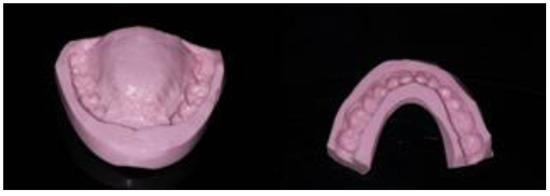

First, alginate impressions were made to obtain diagnostic casts. These casts were mounted in an articulator in order to analyze the case. Face photos and intraoral views were taken and are presented in Figure 1 and Figure 2. The orthopantomogram shown in Figure 3 was realized.